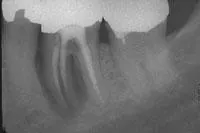

Radiographs usually are not helpful in the detection of cracks. They tend to be unremarkable in most cracks, because these fractures usually run mesiodistally and are not in the plane of the X-ray beam. Sometimes, however, the presence of a complete vertical root fracture can be seen radiographically (see Figure 2). These are cases where the crack extends beyond the crown of the tooth and down into the root. Here you may see a radiolucency involving the lateral aspect or halo surrounding the entire root. This can be differentiated from other radiolucencies by the fact that it surrounds the root uniformly, rather than being located at the portal of exit of the apical foramen or lateral canal. These cases are usually associated with a probing depth corresponding to the extent of the crack. This is the case when the crack is more extensive, long-standing, and the pulp is necrotic. Therefore, there will be no sensitivity to cold or sharp pain, only a dull ache on biting or pressure.7

Upon initiation of root canal therapy, the tooth should be examined under a microscope to further evaluate the extent of the crack. Teeth that are considered restorable are those where the crack is confined to the crown portion of the tooth, coronal to the mucogingival complex. Cracks that extend across the furcation of the tooth, or those extending below the osseous crest, and/or are associated with a corresponding narrow deep pocket are complete vertical root fractures and have a poor prognosis. Teeth with complete vertical root fractures are considered nonrestorable and should be extracted (see Figure 2).9,10